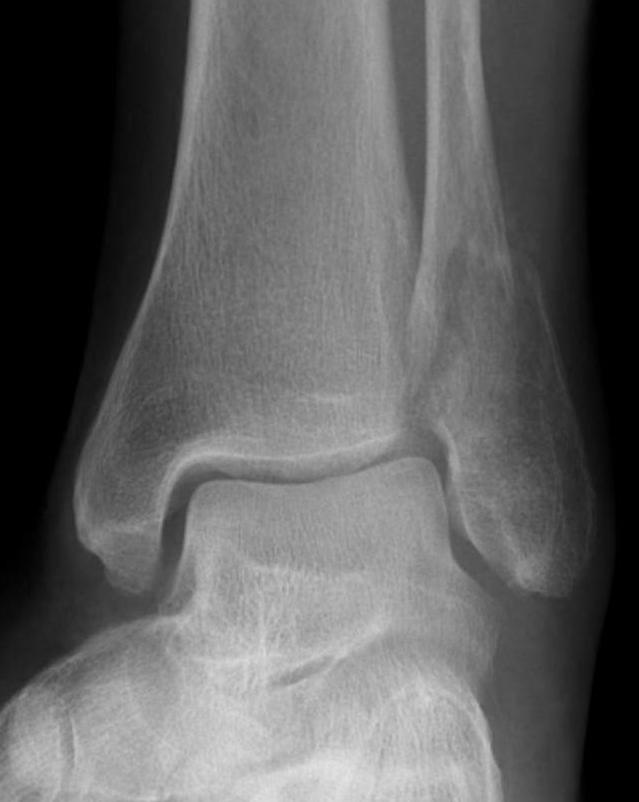

Isolated Weber C fracture

Weber C fracture Weber C fracture with deltoid ligament injury

Maisonneuve injury: proximal fibula with open medial clear space

Definition

Fracture above syndesmosis

Syndesmosis disrupted +/- deltoid ligament

Syndesmotic injury

Xray assessment

| Increased tibio-fibular Clear space | Overlap | Increased medial clear space |

|---|---|---|

|

Medial border of the fibula Lateral border of the posterior tibia (incisura fibularis) Measured 1 cm above the plafond |

Overlap of the fibula and the anterior tibial tubercle | Deltoid ligament injury |

| <5mm AP and mortise |

> 6 mm AP view > 1 mm mortise view |

Maisonneuve / proximal fibular injury |